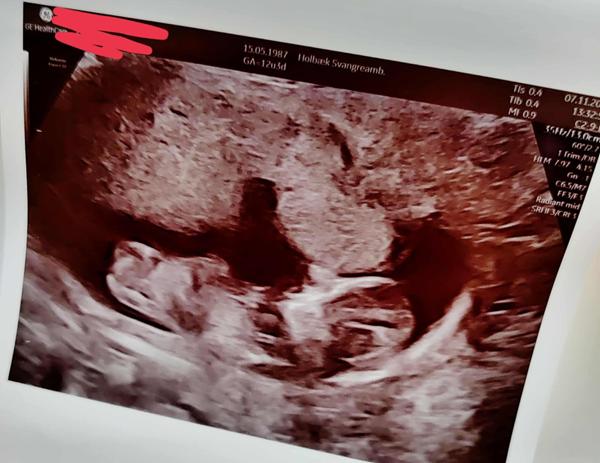

Nu drysser der store jordbunker af, alle steder hun ligger, og jeg render rundt og støvsuger efter hende. På trods af at hun blev blowet efter sine spurter. Jeg burde snart lære at være ligeglad med jord på gulvet, særligt når vi nu går ind i muddertiden smiley

• #77   27. okt 2025 Har taget et billede i de flotte farver udenfor. smiley

okt 2023

#79   28. okt 2025 Pænt billede af dig - men hvor er de der flotte farver? smiley

profilbillede

13 uger i dag, sådan helt præcist.